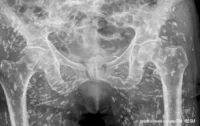

Za otprilike mesec dana, osmorica kriminalaca uspeli su da iskopaju oko 10 metara i došli su na 30 cm od naftovoda. Ali tek što su počeli da se raduju, u hotelu je izvršena policijska racija i svi u njemu su uhapšeni.

Tunel, iako je ojačan drvetom, prolazio je ispod autoputa koji koristi 66.000 vozila dnevno, tako da vlasti sada moraju da napune tunel, pazeći da ne oštete temelje autoputa

Tunel od 9 metara bio je visok 78 centimetara i širok 81 centimetar od podruma hotela. Osumnjičeni su tokom policijskog uviđaja priznali da su planirali da prodaju naftu na dve benzinske pumpe, ali ih se nikada nisu dočepali.